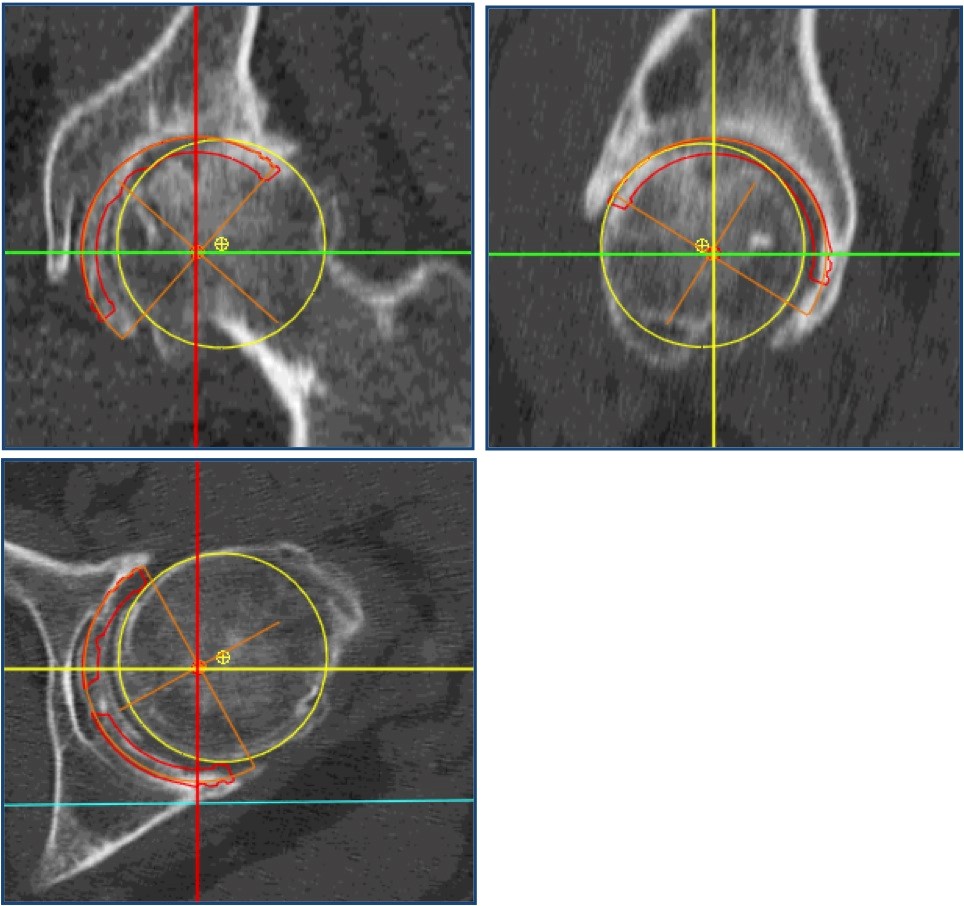

Le scanner couplé à la reconstruction 3D permet enfin d’opter pour une prothèse sur mesure si les mensurations et l’orientation de la hanche à opérer s’éloignent visiblement trop des possibilités de reconstruction avec prothèse standard. La procédure sécurise ainsi le geste opératoire en réduisant les aléas mécaniques.

CHOIX 3D de LA PROTHÈSE PERSONNALISÉE

Le choix de  la partie extraosseuse de l’implant fémoral (col et tête) est dicté par le positionnement des implants cotyloïdien et fémoral, et par la restauration voulue de l’anatomie.

Il impose le plus souvent une modularité en 3 éléments : tige, col, tête.

Les « réglages » sont possibles dans tous les plans grâce à la gamme permettant de choisir :

• l’axe du col (neutre, varus, valgus, antéversion, rétroversion).

• La longueur de col (court, long).

• La « profondeur » de tête (= choix supplémentaire de longueur).

• L’implant fémoral peut, lorsque l’anatomie du patient, très atypique, ne peut être restaurée avec les implants « prêts-à-porter » disponibles, être fabriqué sur mesures.